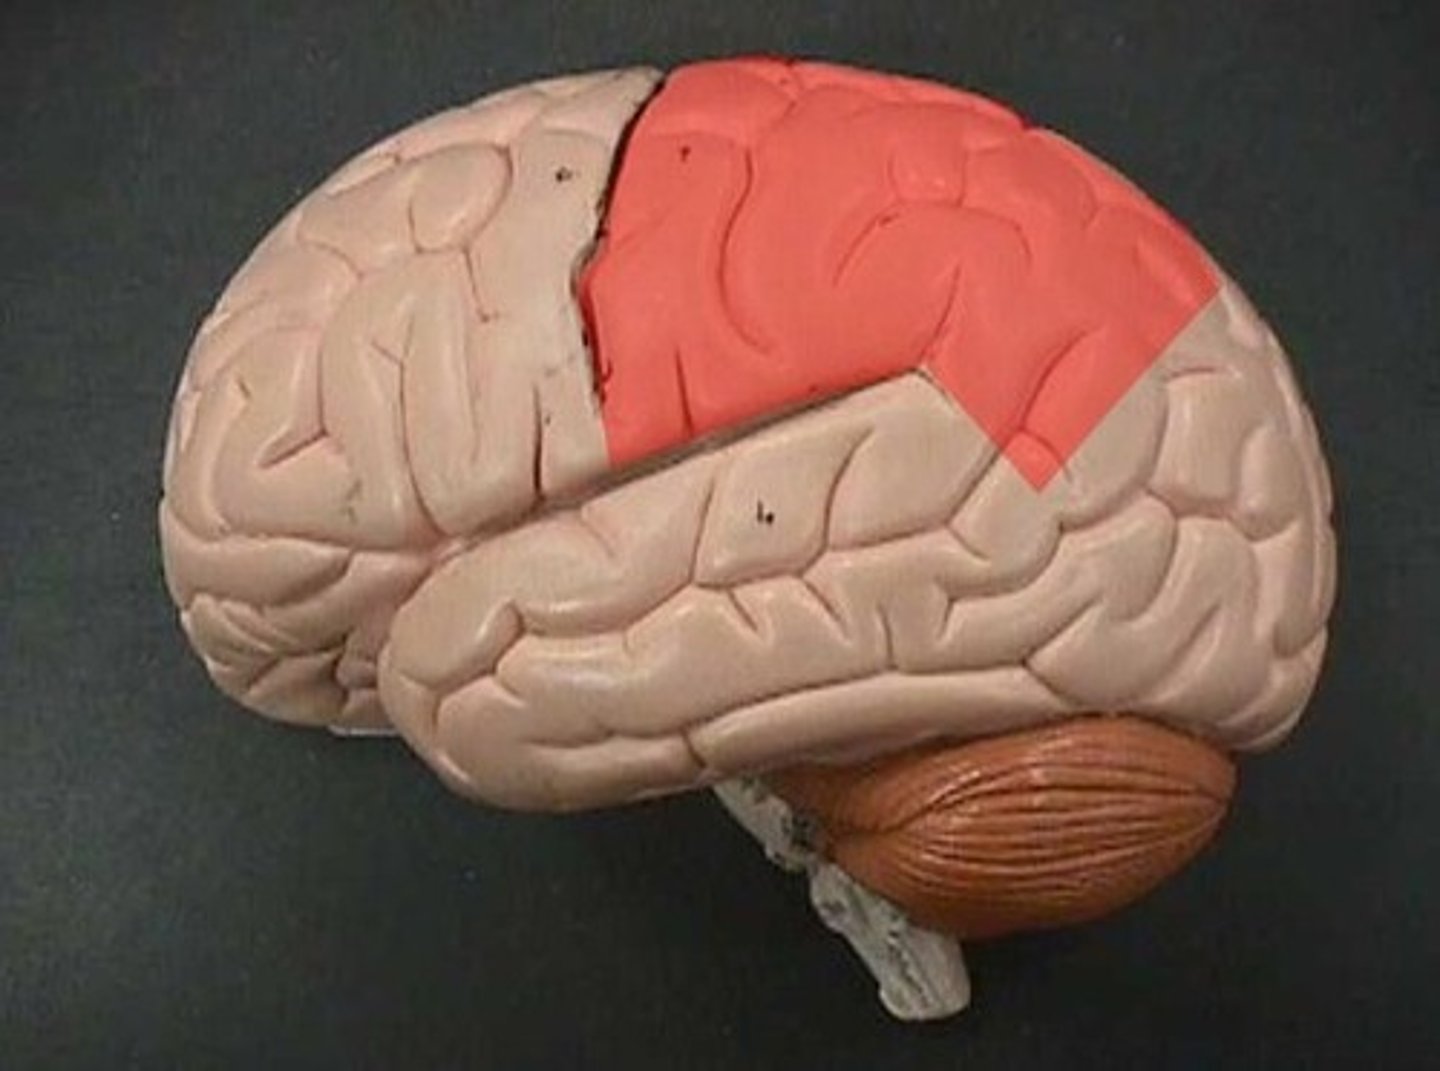

frontal lobe

parietal lobe

Premotor cortex